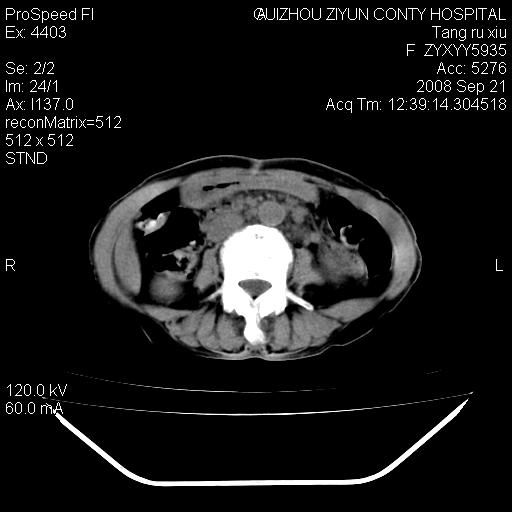

f、57岁,上腹痛.2月,近来胸闷。2月前在外院摄胸片示左侧胸腔少量积液。

(患者腹痛入院,欲吐,临床医生说禁饮,所以没有口服对比剂)

肝脏大小形态尚可,其实质内可见多发大小不等的低密度影,边缘模糊。肝门区结构紊乱,腔静脉腹主动脉旁可见多发软组织密度影,部分融合成团块状,并向下延伸。胰腺及十二指肠结构显示不清。腹腔内脐后肠管走形僵硬,管壁可见增厚。盆腔内可见多个淋巴结影。所扫层面左侧胸腔可见大量弧形水样密度影,其内侧可见被压缩的肺组织影。左侧胸壁可见一小结节样软组织密度影,边缘模糊。心脏纵隔向右侧移位。心脏包膜内可见囊样低密度影,其内侧心房室周围可见一圈气体样密度影。纵隔内大血管旁可见多发软组织团块影,部分融合。

1.腹膜后淋巴瘤侵及肝脏,肺内及纵隔内多发转移。2.左侧大量胸腔积液并压缩性肺不张。3.心包脓肿可能,转移不除外。4.脐后局部肠管管壁增厚,考虑炎症可能,肿瘤不除外。